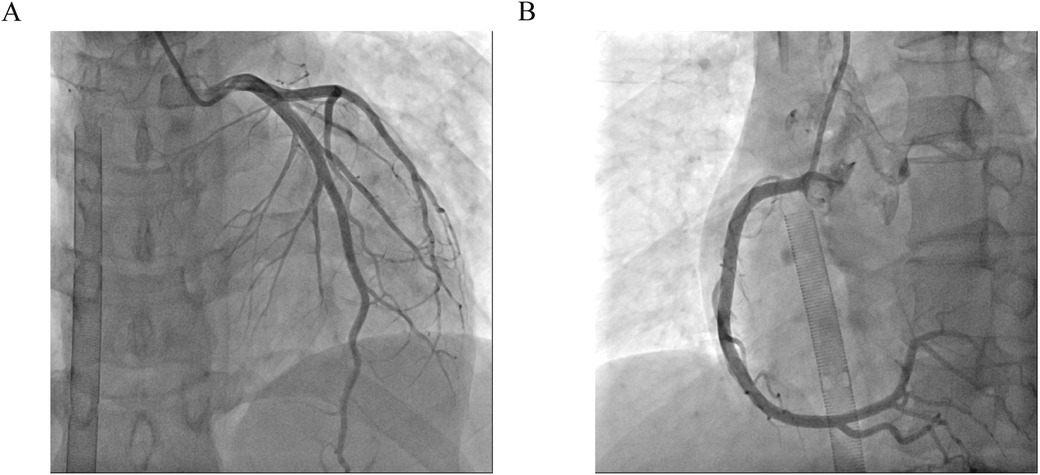

One day after admission, the patient's vital signs were unstable and her blood pressure remained low despite high doses of norepinephrine and m-hydroxyamine. Physical examination revealed scattered red maculae and maculopapules on the trunk and limbs, accompanied by iridoid lesions, blisters, and oral mucosal erosion (Figure 2). Echocardiography examination indicated a significant decrease in Ejection fraction (24%). A review of laboratory tests showed: WBC 6.6 × 109/L, CRP 20.2 mg/L, ALT 225 U/L, LDH 658 U/L, cTnI 20.9 ng/ml, CK 803 U/L, Lactate 6.62 mmol/L, NT-proBNP 6,690 ng/L. Considering the risk of cardiac arrest remains high, endotracheal intubation, V-A ECMO, and emergency coronary angiography were performed. Coronary angiography showed no obvious coronary vessel stenosis (Figure 3). At the same time, we performed extensive hematological tests to determine the cause of the erythema multiforme. Blood cultures were negative for bacteria and fungi. Immunological tests such as antinuclear antibodies, anti-double-stranded DNA antibodies and rheumatoid factors were negative. COVID-19 polymerase chain reaction was negative. HIV, Hep A, B, C and Treponema pallidum serologies were negative. Coxsackie virus, adenovirus, influenza A virus, influenza B virus, human parainfluenza virus, respiratory syncytial virus, Mycoplasma pneumoniae, chlamydia pneumoniae were negative. However, Chemiluminescence showed that herpes simplex virus-1 (HSV-1) was positive. Therefore, we considered that the patient had severe myocarditis and erythema multiforme due to infection with HSV-1 virus. We gave acyclovir needle antiviral and methylprednisolone needle anti-inflammatory. After the initiation of ECMO, the patient's blood pressure significantly increased and gradually stabilized at a systolic blood pressure of 90–168 mmHg and a diastolic blood pressure of 64–112 mmHg. Arterial blood gas analysis showed a significant improvement in acidosis. Therefore, we discontinued all vasoactive medications on the second day following the initiation of ECMO. Four days after the initiation of ECMO, the flow rate was reduced to 1.2 L/min, the patient's blood pressure remained relatively stable, blood gas analysis indicated good tissue perfusion, and follow-up echocardiography showed that the ejection fraction (EF) had recovered to 42%. We concluded that the criteria for ECMO withdrawal had been met, and ECMO was removed four days after its initiation. The day after ECMO was removed, the patient was then scheduled for a cardiac magnetic resonance imagery (CMRI) examination. Cardiac magnetic resonance T2-weighted imaging shows diffuse hypersignal in the left ventricular wall (Figure 4). Finally, the patient's symptoms gradually improved, the rash gradually disappeared on the seventh day, and she was discharged successfully after 2 weeks of treatment. The specific clinical process is shown in Supplementary Image 1. The patient has now been under observation for a period of one year, during which time she has attended five outpatient reviews at the hospital. No significant abnormalities have been observed in the patient's skin, troponin levels, electrocardiogram, or cardiac ultrasound. Furthermore, the patient has not continued any medications for the treatment of ring erythematosis or myocarditis.

Figure 3. Coronary angiography. (A) Left coronary artery showed no obvious coronary vessel stenosis. (B) Right coronary artery showed no obvious coronary vessel stenosis.